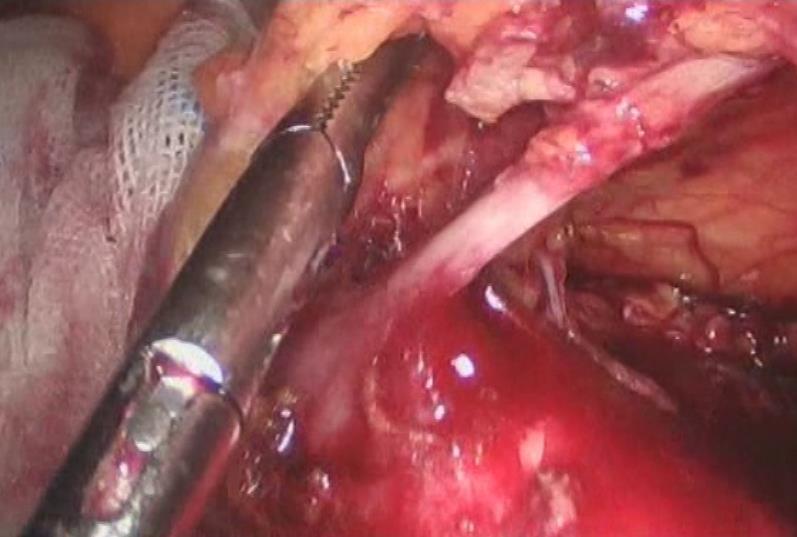

结直肠癌是我国常见的恶性肿瘤,患者就诊时多已为晚期或局部晚期。由于肿瘤瘤体巨大,侵犯邻近脏器,多个脏器受累,临床处理有一定困难。部分外科医生面对晚期结直肠癌时选择放弃手术。但事实上,多学科综合治疗能使晚期或局部晚期患者获得相对好的治疗结果,不应该轻易放弃合理的外科手术。对于肿瘤巨大但没有远处转移,有多脏器受累的患者,直接手术切除困难,可以考虑进行术前的辅助治疗。外科手术原则是在能够达到R0切除的基础上,尽量保留脏器的功能,进行合理的区域淋巴结清扫。

这老太太87岁,肠癌梗阻,病情较晚,在其他医院不敢做,准备放弃了,来我院经过处理后,微创手术解决问题。